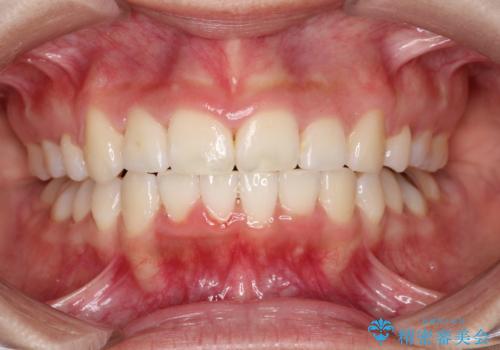

- 前歯のがたつきと出っ歯が気になるとのことで来院されました。

上顎の前から4番目の歯を両側合計2本抜歯して矯正することとなりました。

抜歯をして矯正をすることで、前歯を後方に移動させ、ガタガタを改善することができました。